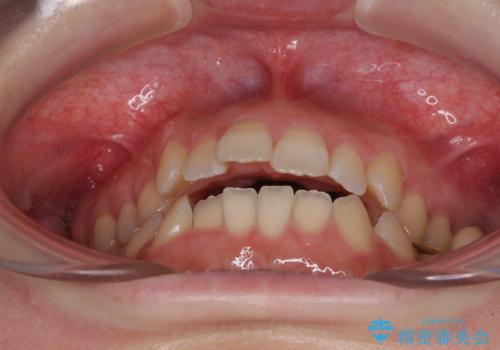

オープンバイトと前歯のデコボコをインビザライン矯正で解消

- 前歯の開咬を気にして来院された患者様です。

開咬の治療は、前歯を閉じるように動かすとともに、上下臼歯を圧下(骨内にめり込ませる)させることで進めて行きます。

インビザラインは臼歯の圧下を効果的に行えるため、インビザラインを用いて矯正治療を行うこととしました。